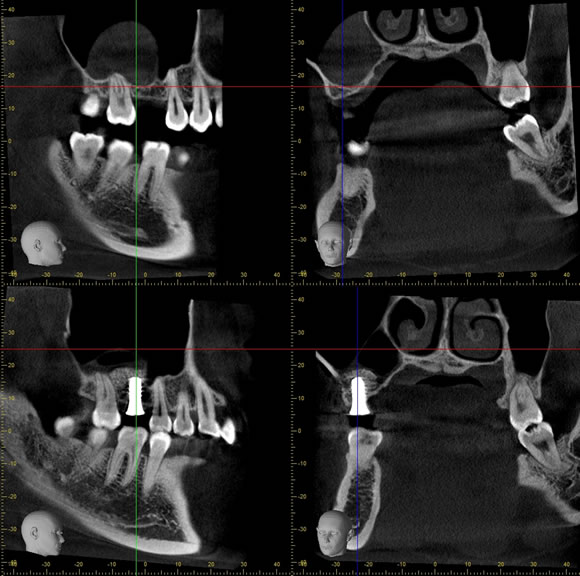

術後2年経過の最も典型的なエナメル上皮種です。再発率が非常に高いので最低でも5年以上の経過観察が必要となります。今回は摘出術と一部健常域まで辺縁切除(骨を削る)を行いました。

1枚目(パノラマ)上:術前 下:術後 摘出部分に新生骨を認めます。

2枚目(CT)上:術前 下:術後 摘出部分に新生骨を認めます。